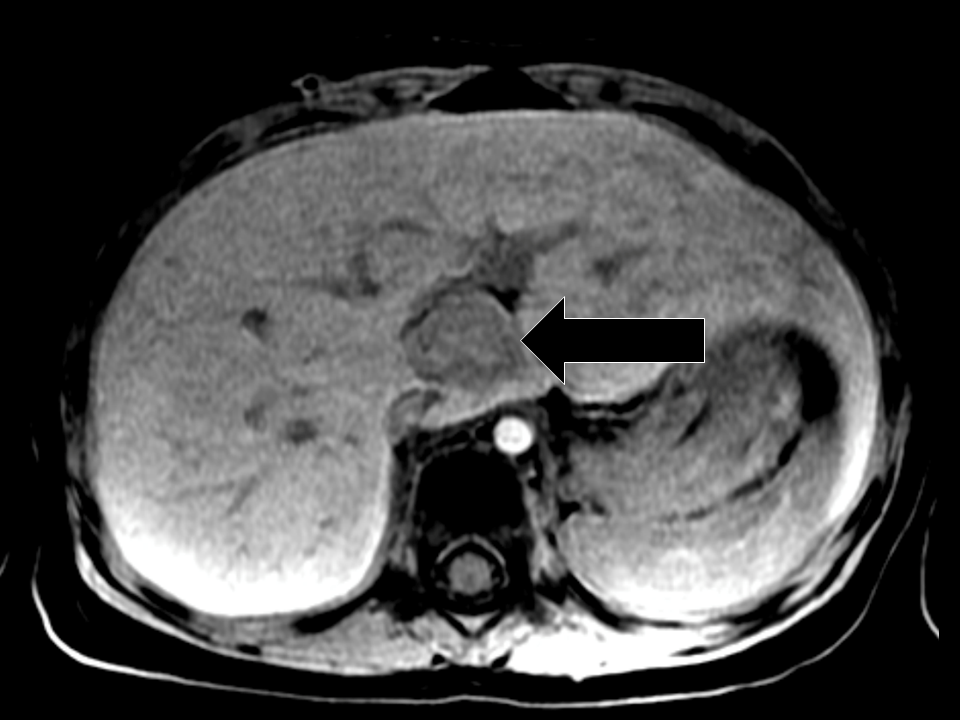

Comparison of CT and MRI findings. Note the ability of MRI with Eovist Eovist Uptake (a) uptake by hyperplastic hepatocytes, (b) uptake by tumor cells, (c) retention in extracellular space, (d) peritumoral retention, and (e) biliary enhancement in the tumor. hepatobiliary contrast reduces the ability to identify portal vein thrombus. Infiltrative hcc may be harder to visualize than with extracellular. screen patients for acute kidney injury and other conditions that may reduce renal. Eovist Uptake.